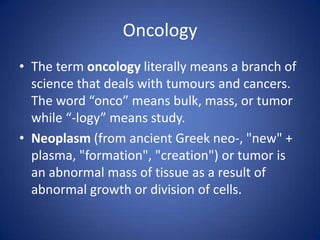

Oncology is the study of tumors and cancers. Neoplasms are abnormal masses of tissue that result from abnormal cell growth or division. Benign tumors are non-cancerous, while malignant tumors are cancerous. Tumors are classified based on their tissue of origin and whether they are benign or malignant. Oncology examines the characteristics, structures, and significance of features of neoplastic cells and tumors under the microscope.

- 1. Oncology • The term oncology literally means a branch of science that deals with tumours and cancers. The word “onco” means bulk, mass, or tumor while “-logy” means study. • Neoplasm (from ancient Greek neo-, "new" + plasma, "formation", "creation") or tumor is an abnormal mass of tissue as a result of abnormal growth or division of cells.